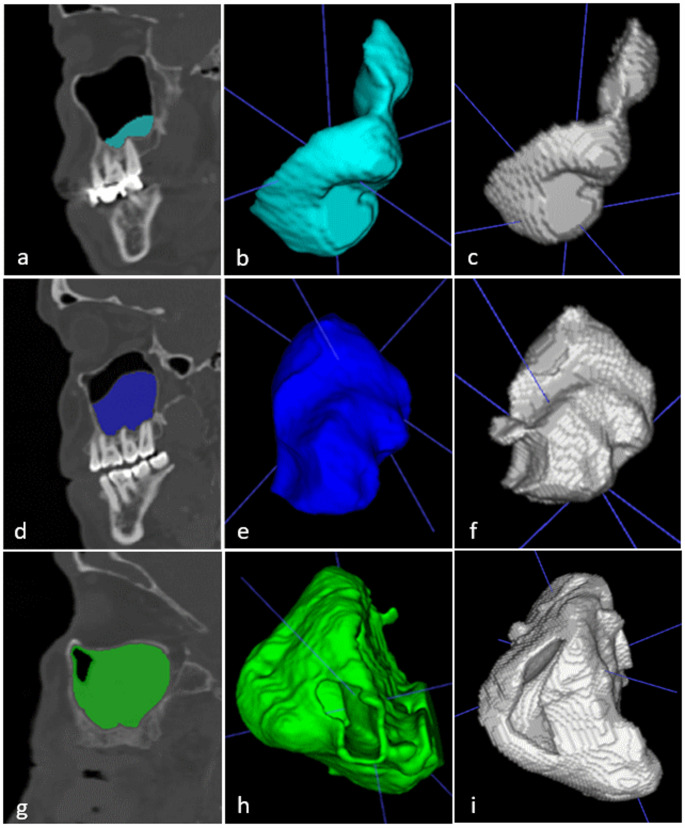

Methods: A dataset comprising 1000 maxillary sinuses (MS) from 500 patients was analyzed using CBCT. Sinuses were categorized based on the presence or absence of pathology, followed by segmentation of the maxillary sinus. Manual segmentation masks were generated using the semiautomatic software ITK-SNAP, which served as a reference for comparison. A convolutional neural network (CNN)-based machine learning model was then implemented to automatically segment maxillary sinus pathologies from CBCT images. To evaluate segmentation accuracy, metrics such as the Dice similarity coefficient (DSC) and intersection over union (IoU) were utilized by comparing AI-generated results with human-generated segmentations.

Results: The automated segmentation model achieved a Dice score of 0.923, a recall of 0.979, an IoU of 0.887, an F1 score of 0.970, and a precision of 0.963.